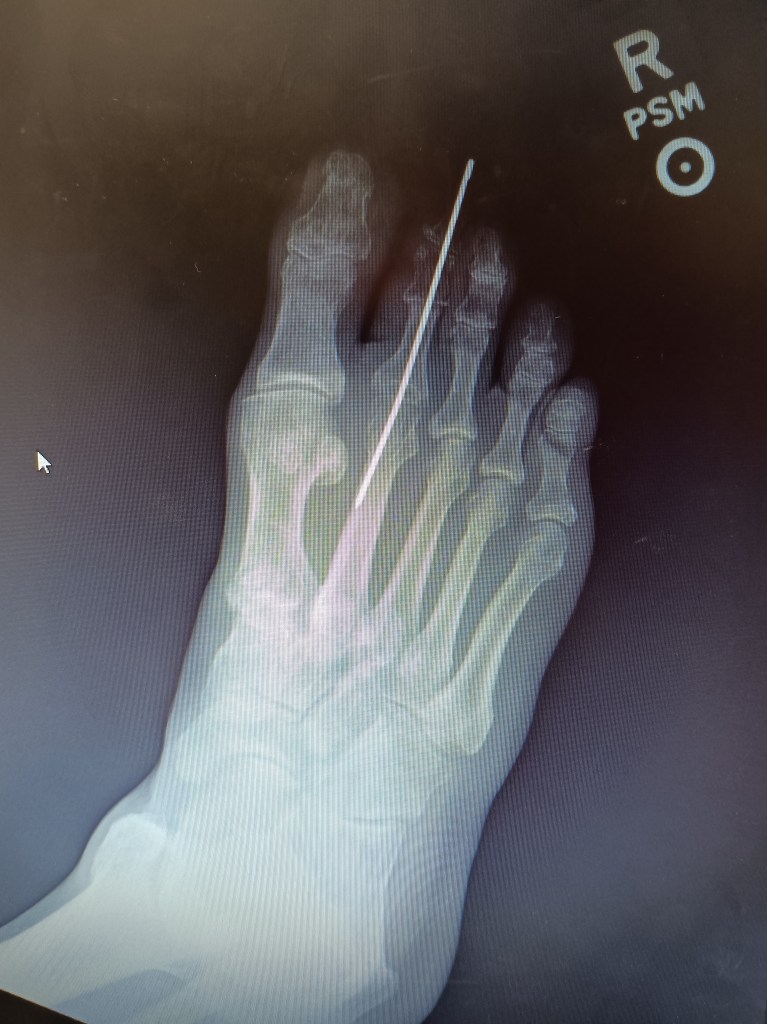

For about a year I’ve been developing another hammer-toe on the next-to-largest toe of my right foot. Hammer-toe is a disorder of the toe joints causing the joint to knuckle up in a close to 90-degree bend, causing pain when walking.

From Wikipedia: ‘a deformity of the proximal interphalangeal joint of the second, third, or fourth toe causing it to be permanently bent, resembling a hammer’

‘Hammer toe’ is a joint dislocation that can only be corrected, in its ‘frozen’ state, by surgery of the affected toes, ligaments and muscles. The surgeon removes bone so the toes can lie flat again and pins are inserted to make them heal that way. The pins will be removed later.’